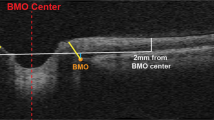

Posterior segment perfusion culture

Human donor eyes were harvested within 6–12 h of death and cultured within 24 h in the TAS model23. Culture media consisted of a neurobasal perfusion medium, which was prepared fresh prior to receipt of the eyes. The neurobasal perfusion medium was prepared according to previously established protocols42,43. Briefly, neurobasal/B27 medium (ThermoFisher Scientific) was utilized with 100 U/ml penicillin (Sigma Aldrich), 100 μg/ml streptomycin (Sigma Aldrich), 1 mM pyruvate (ThermoFisher Scientific), 2 mM glutamine (ThermoFisher Scientific), 5 μg/ml insulin (Sigma Aldrich), 100 μg/ml transferrin (Sigma Aldrich), 100 μg/ml bovine serum albumin (Sigma Aldrich), 60 ng/ml progesterone (Sigma Aldrich), 16 μg/ml putrescine (Sigma), 40 ng/ml sodium selenite (Sigma Aldrich), 40 ng/ml thyroxine (Sigma Aldrich), 40 ng/ml tri-iodothyronine (Sigma Aldrich), 5 μM forskolin (Sigma Aldrich) and 1% human serum (Sigma Aldrich). Under sterile conditions, whole eyes were initially soaked in a povidone-iodine solution for 2 min followed by a wash in sterile phosphate-buffered solution (PBS). Excess adnexa was dissected from the globe, and the eye was bisected at the equator into anterior and posterior segments. Vitreous humor, lens, and the optic nerve sheath were removed from the posterior segment 2 mm from the posterior end of the globe for all samples. Additional sclera was trimmed, if necessary, to ensure a proper fit over the rounded dome of the IOP chamber (bottom compartment) with the ON facing upwards. The chamber dome is slightly flattened at the top which ensures effective perfusion of the retina. The posterior segment was secured with a circular ring sealed using an epoxy resin O-ring with four screws, ensuring a tight seal. Inflow and outflow tubing was inserted into their respective ports, and the posterior eye cup was manually infused with neurobasal perfusion medium using the push/pull method to remove any air bubbles through the outflow port. The ICP chamber (top compartment) was subsequently placed directly on top of the IOP chamber and sealed with four screws, ensuring that the ON was encased within the ICP chamber. Inflow and outflow tubing was inserted and the ICP chamber was infused with neurobasal perfusion medium as described above. The entire TAS unit was incubated at 37 °C in 5% CO2 for the duration of the perfusion study. Each chamber was connected to its own hydrostatic pressure transducer attached to a multichannel bridge amplifier. Each pressure transducer was manually calibrated just prior to the study using a two-point liquid calibration method. Medium was perfused through the inlets at an adjustable flow rate using an automated syringe pump system to maintain the desired pressure, and the conditioned medium was collected every 48–72 h from the chamber outlets. Pressure data was recorded every 1 min and averaged over a 24-hour period with the LabChart software system. Flow rates were adjusted manually to maintain the targeted pressures. Basic flow rates ranged from 100 to 300 uL/min to mimic the approximate range of physiologic flow rates22. The mean and standard deviations of IOP, ICP, and TLPD were calculated for every 24-hour period. After a 10 to 12-day period, retinal and ON tissue was collected for further analysis. Measurements were taken from distinct samples.